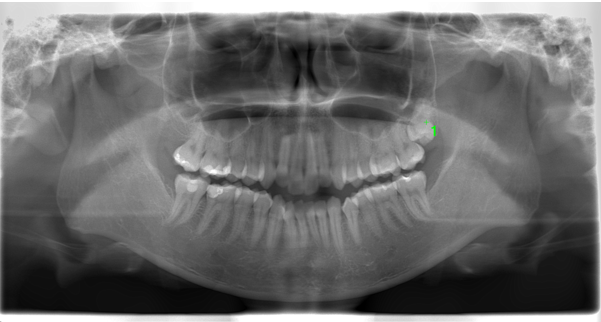

Before

| 通院時の年齢 | 25歳 |

| 性別 | 女性 |

| 通院回数 | 2.5年 |

| 通院目的 | 歯列矯正 |

| 処置内容 | インビザラインによるマウスピース矯正 |

| 費用 | 80万 |

| デメリット・注意点 | 患者の協力に起因する 今回親知らずのの萌出も左上では必要のため出てこない場合は更に必要が2万加算される可能性があった |